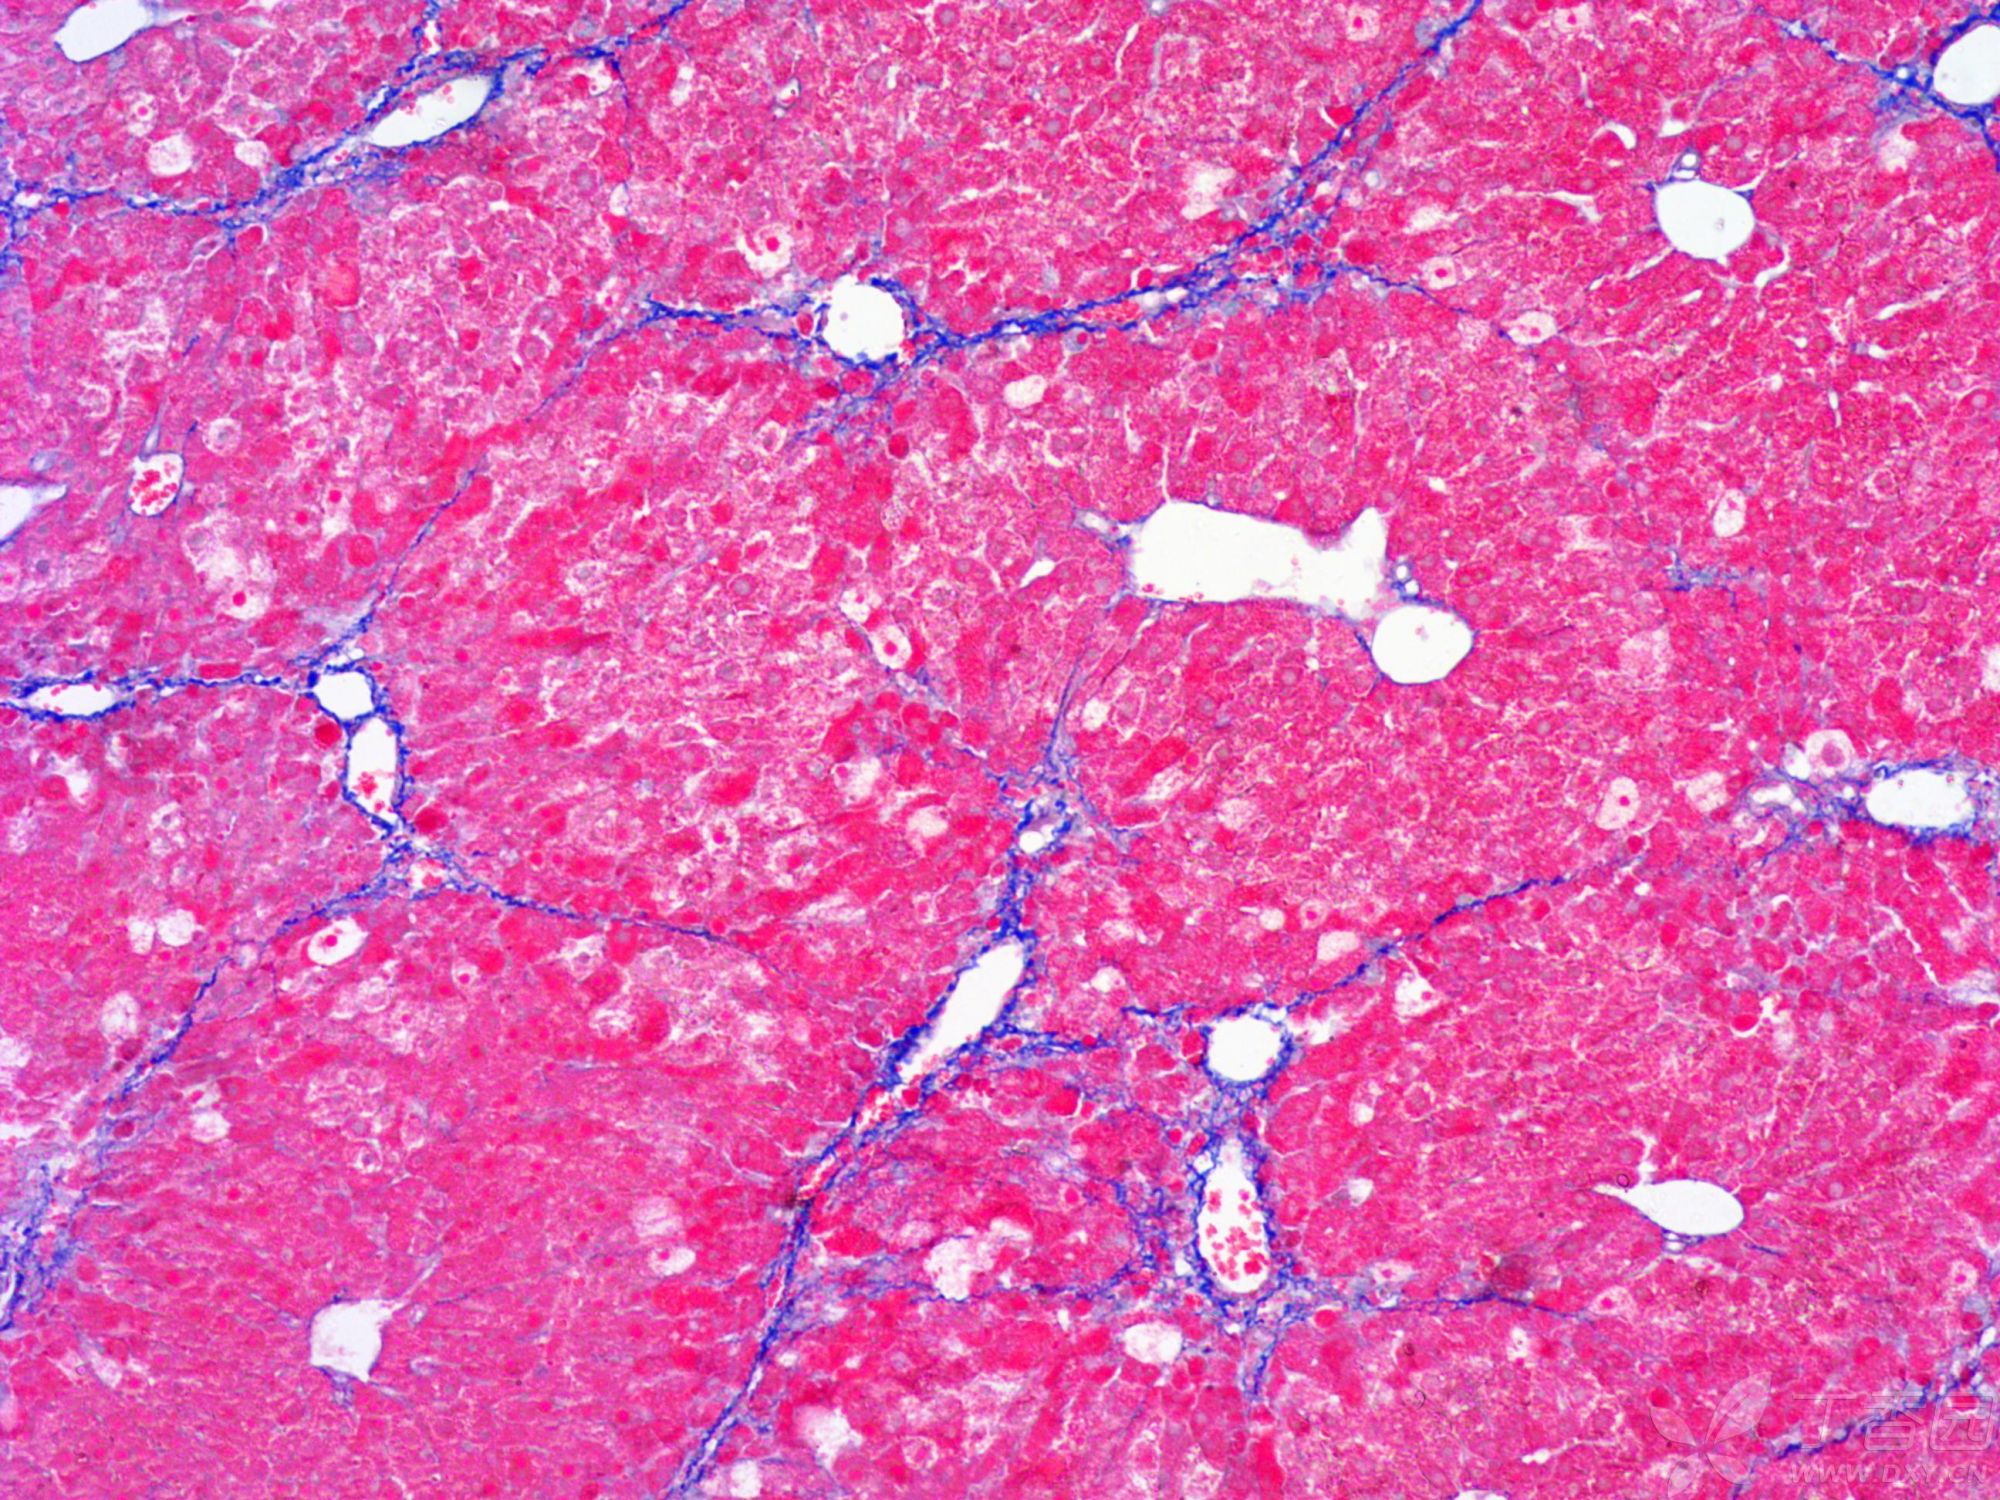

MASSON染色的原理主要基于陰離子染料分子的大小和組織滲透性的關(guān)系。染料分子的大小決定了其能夠滲透進(jìn)入的組織類型。小分子量的染料能夠穿透結(jié)構(gòu)致密、滲透性低的組織,而大分子量的染料則只能進(jìn)入結(jié)構(gòu)疏松、滲透性高的組織。在MASSON染色中,由于肌纖維間隙較小,麗春紅等小分子染料能夠滲透其中并染色,使其呈現(xiàn)紅色;而膠原纖維間隙較大,大分子量的苯胺藍(lán)等染料能夠進(jìn)入并染色,使其呈現(xiàn)藍(lán)色或綠色。這種染色方式使得我們能夠清晰地觀察到并區(qū)分這兩種不同的組織成分。

小鼠纖維化